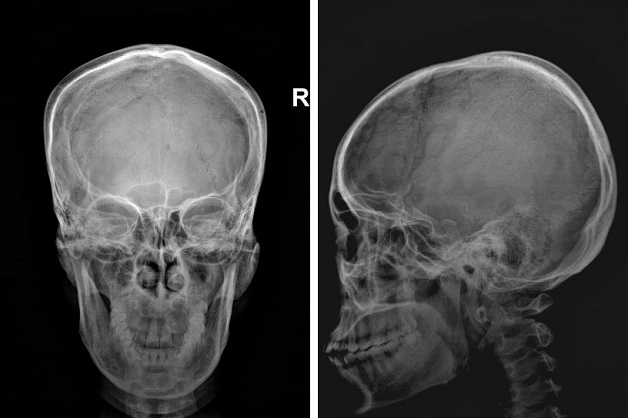

Kỹ thuật chụp X quang thường quy là một kỹ thuật chẩn đoán hình ảnh được sử dụng từ rất lâu, giúp đánh giá nhiều tổn thương, gồm cả tổn thương cột sống và sọ não.

Trước đây, khi chưa có các phương pháp chẩn đoán hình ảnh tiên tiến như chụp cắt lớp vi tính hay chụp cộng hưởng từ, thì chụp X quang là phương pháp chẩn đoán hình ảnh hệ thần kinh và nhiều cơ quan khác trong cơ thể được áp dụng phổ biến.

Kỹ thuật chụp X quang hệ thần kinh gồm:

– Chụp toàn bộ hộp sọ với các mặt phẳng trán (tư thế thẳng), mặt phẳng trục (tư thế hirtz), mặt phẳng dọc giữa (tư thế nghiêng).

– Chụp phóng đại trực tiếp một vùng

– Chụp cột sống từng vùng

– Chụp X quang tư thế động

Chụp X quang giúp chẩn đoán tốt hơn các vấn đề ở phần xương như sọ và cột sống, tuy nhiên các phần bị xương che khuất, phần mềm khó chẩn đoán.

Hình ảnh chụp X quang sọ não thẳng, nghiêng. (hình minh họa)